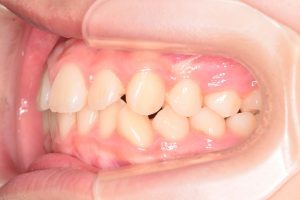

左側

0000000004

0000000025

0000000076

1期治療開始時(2024年3月)

2期治療開始時(2024年11月)

保定開始時(2025年1月)の写真です。